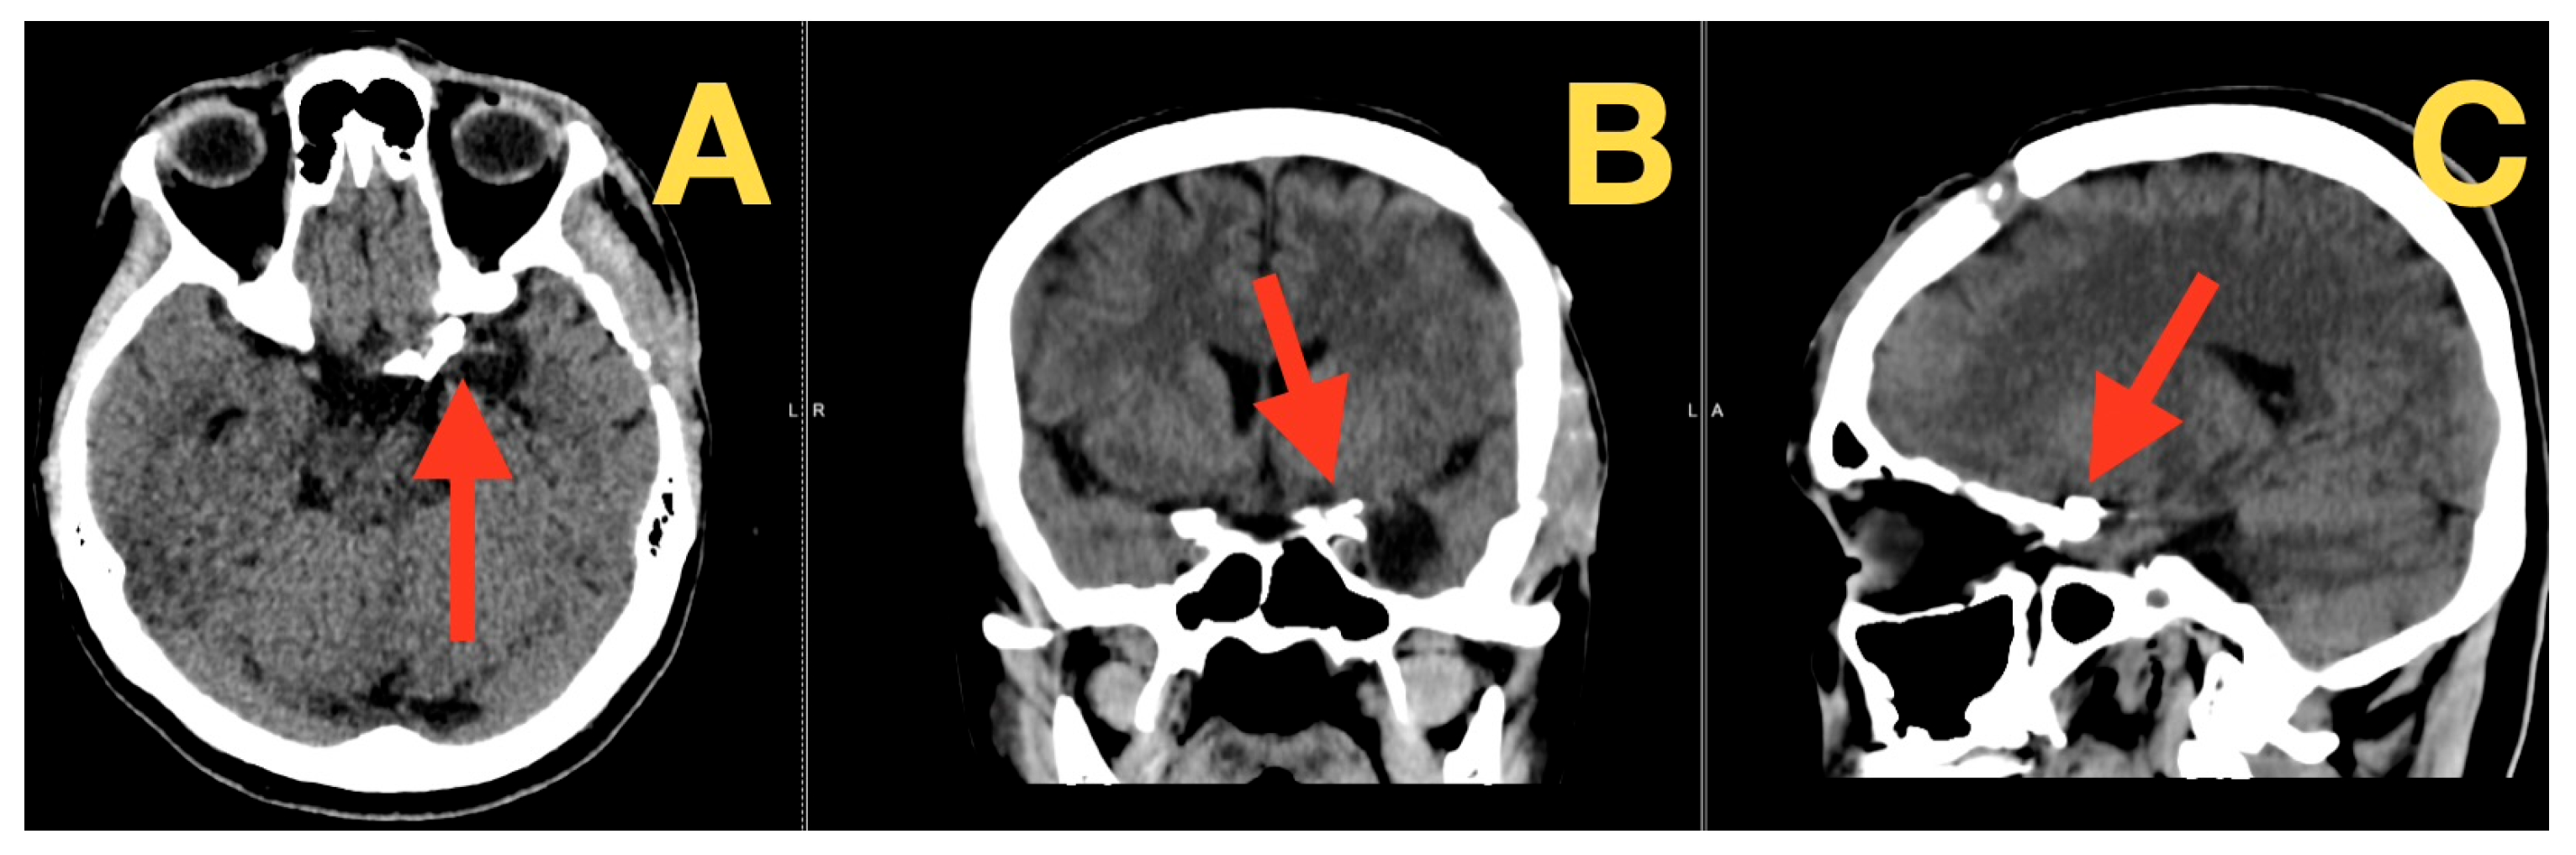

2. Case Presentation